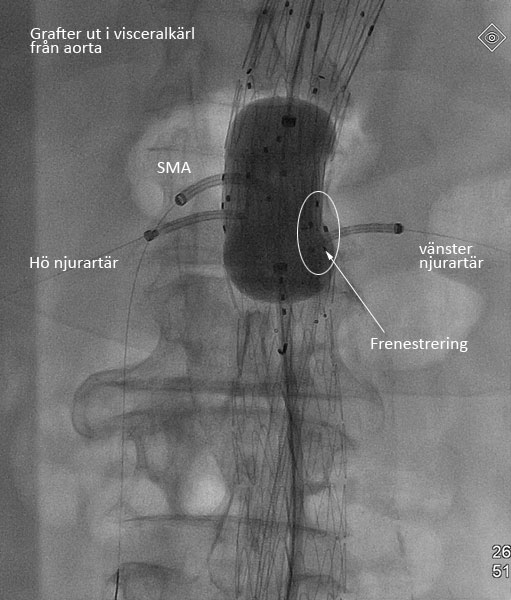

- Advanta stentgraft eller BeGraft (vanligen 6×22 till njurartärer och 7×32 till SMA- och a. truncus artäravgång)

- Innan den proximala graften släppts ska alla fenestreringar kateteriseras via 20F introducern (Extra-Large Check-Flo) i kontralaterala ljumsken.

CODA-ballong Avgångsartärerna (visceralkärl) från aorta kateteriseras med Sos Omni 0 kateter och en Terumo-ledare.

- Vald visceralkärls-graft (Advanta, BeGraft, etc.) förs på över Storq-ledare och läggs på plats utan att graften expanderas.

- Denna procedur upprepas för kateterisering av alla aktuella visceralkärl.